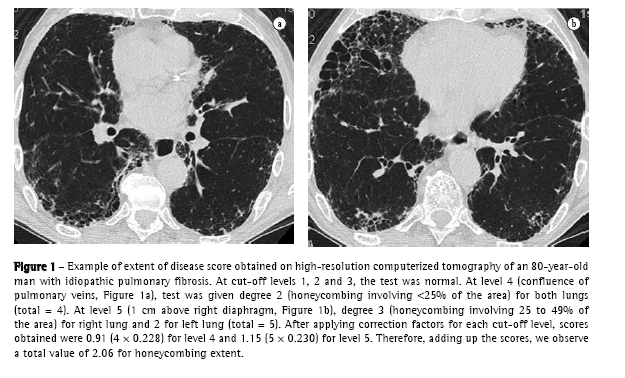

In the end, TID, reticular abnormality/honeycombing and ground-glass opacity levels were obtained by totaling the scores for each level. An example of how these scores were obtained is shown in Figure 1.

c) the following technique was used for HRCT: GE equipment, HISPEED model; 1-mm thick slices, at 1.5 s intervals and increased by 10 mm; image reconstruction with a 512 × 512 pixel matrix, using a high resolution algorithm; 1000 HU width window; −700 HU medium window level. Interpretation of tomographic findings was performed according to a consensus among four radiologists with extensive experience in interstitial disease. In the absence of histologic material, the diagnosis of IPF by HRCT was accepted only upon concordance of all readers and if all clinical and functional criteria described above were met. An initial overall analysis of the HRCT (without considering cut-off levels) was conducted, in search of the following findings: nodules, ground-glass opacities, reticular abnormality, honeycombing (cysts 3 mm and 3 mm), traction bronchiectasis, air trapping areas and emphysema.(18,19) Subsequently, the HRCT was evaluated as to the extent and intensity of interstitial lung involvement, considering five cut-off levels: 1) origin of major vessels; 2) aortic arch level; 3) carina; 4) confluence of pulmonary veins; and 5) 1 cm above the right diaphragm.(6,19-21) Using a semiquantitative evaluation system, each of these levels (right and left, separately, totaling 10 levels) was analyzed as to the following aspects:

For the analysis of HRCT findings, estimated pulmonary involvement was obtained using an influence factor ('weight') to correct different pulmonary volumes at each level, as follows(19):

origin of major vessels - weight = 0.129;

aortic arch level - weight = 0.190;

carina - weight = 0.222;

confluence of pulmonary veins - weight = 0.228; and

1 cm above the right diaphragm weight = 0.230.